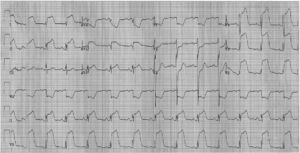

以往臨床上根據心電圖出現病理性Q波,ST段移位及T波改變,將心肌梗死分為急性期、亞急性期和陣舊性心肌梗死三個時期,但近年來發現,在本病早期多不能顯示心肌梗死的典型心電圖變化,往往只有ST-T改變,醫學教育網原創其中ST段抬高是急性心肌梗死(AMI)的最早期心電圖表現之一,ST段抬高特性和呈規律性演變過程是診斷AMI的重要標準。